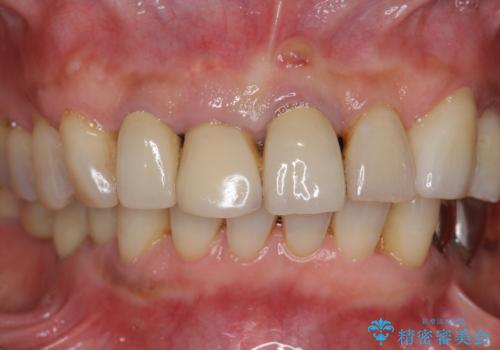

2. ぐらつく前歯 ブリッジ治療の治療中